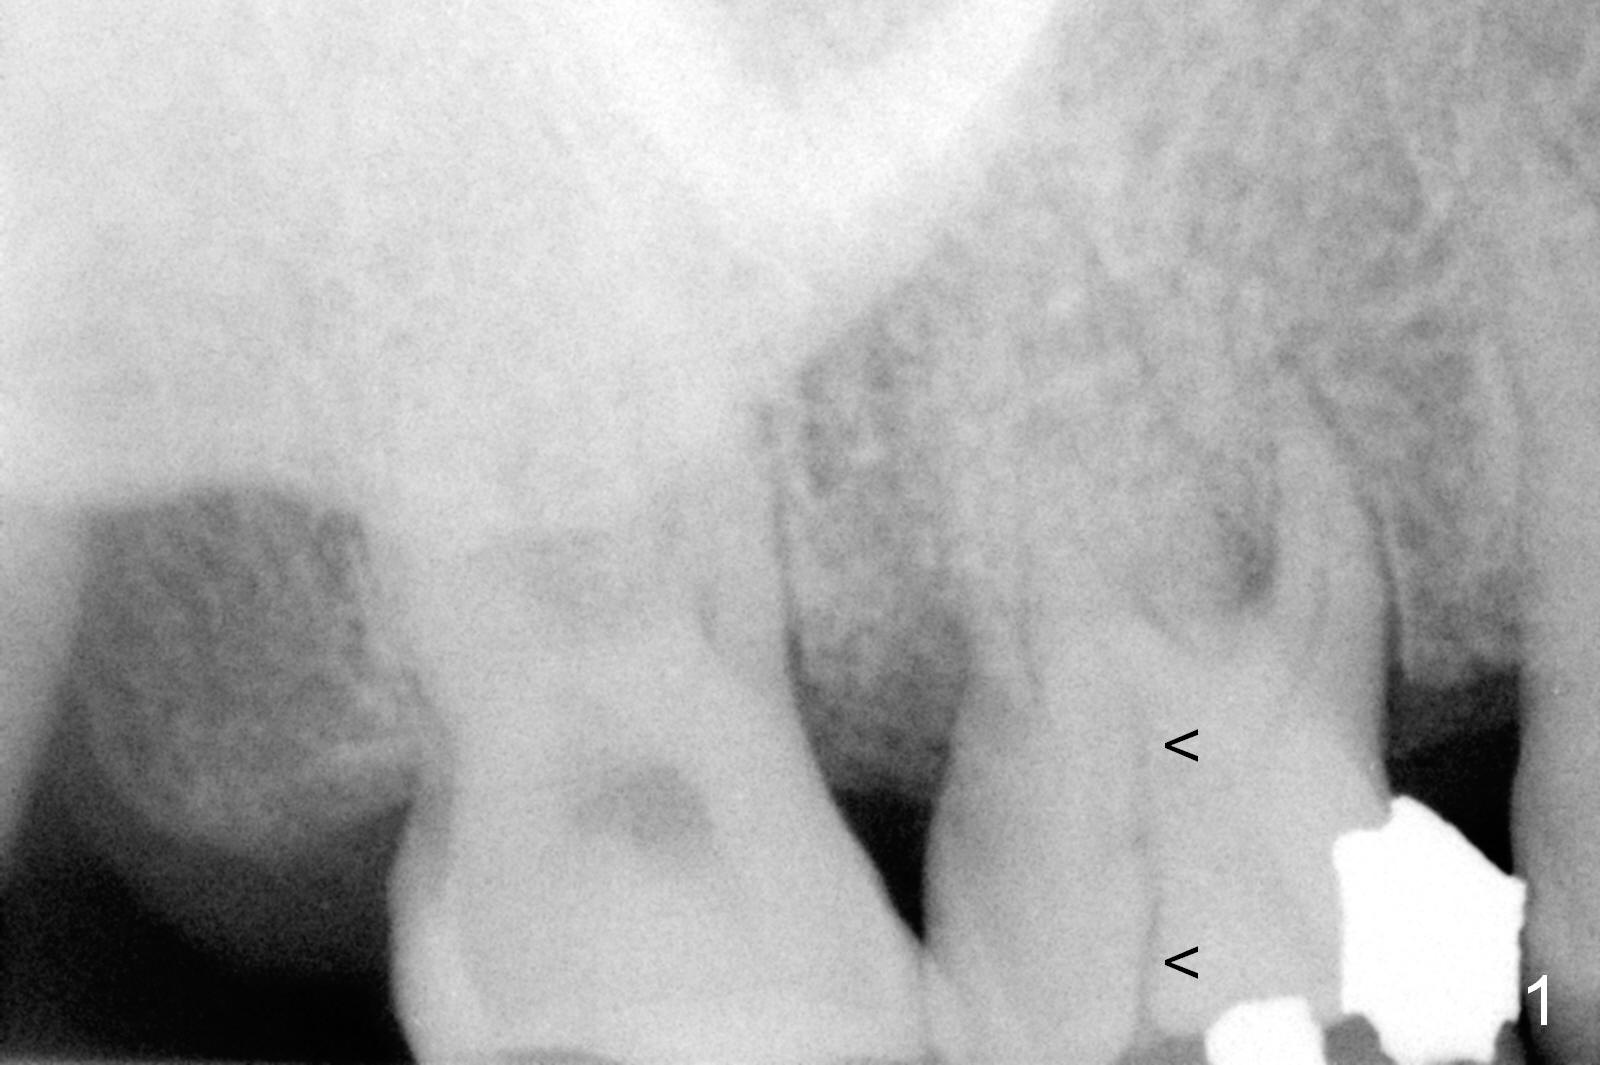

![]() UF Immediate Implant for Upper 1st Molar A 52-year-old lady has chewed on the right side for several years, because of loss #14. The mesiolingual cusp of the tooth #3 fractures subgingivaly (Fig.1 <). The tooth has trifurcated roots. Surgical handpiece may be used for sectioning if simple extraction with proximators is not feasible. After extraction, granulation tissue may be present in the palatal wall, next to the crack line. If the defect is large, use Osteotape for repair before bone graft. The socket will be packed with Metronidazole 2% Xylocaine 1:50,000 Epinephrine for 3 times. Osteotomy is initiated in the middle of the septum using UF cassette drills until 1 size smaller than the implant planned (Fig.2). If the implant is placed in the middle of the edentulous space, a cemented abutment as large as 7.5x4(3) mm is placed. Return to Upper Molar Immediate Implant Xin Wei, DDS, PhD, MS 1st edition 09/19/2015, last revision 01/19/2019 |